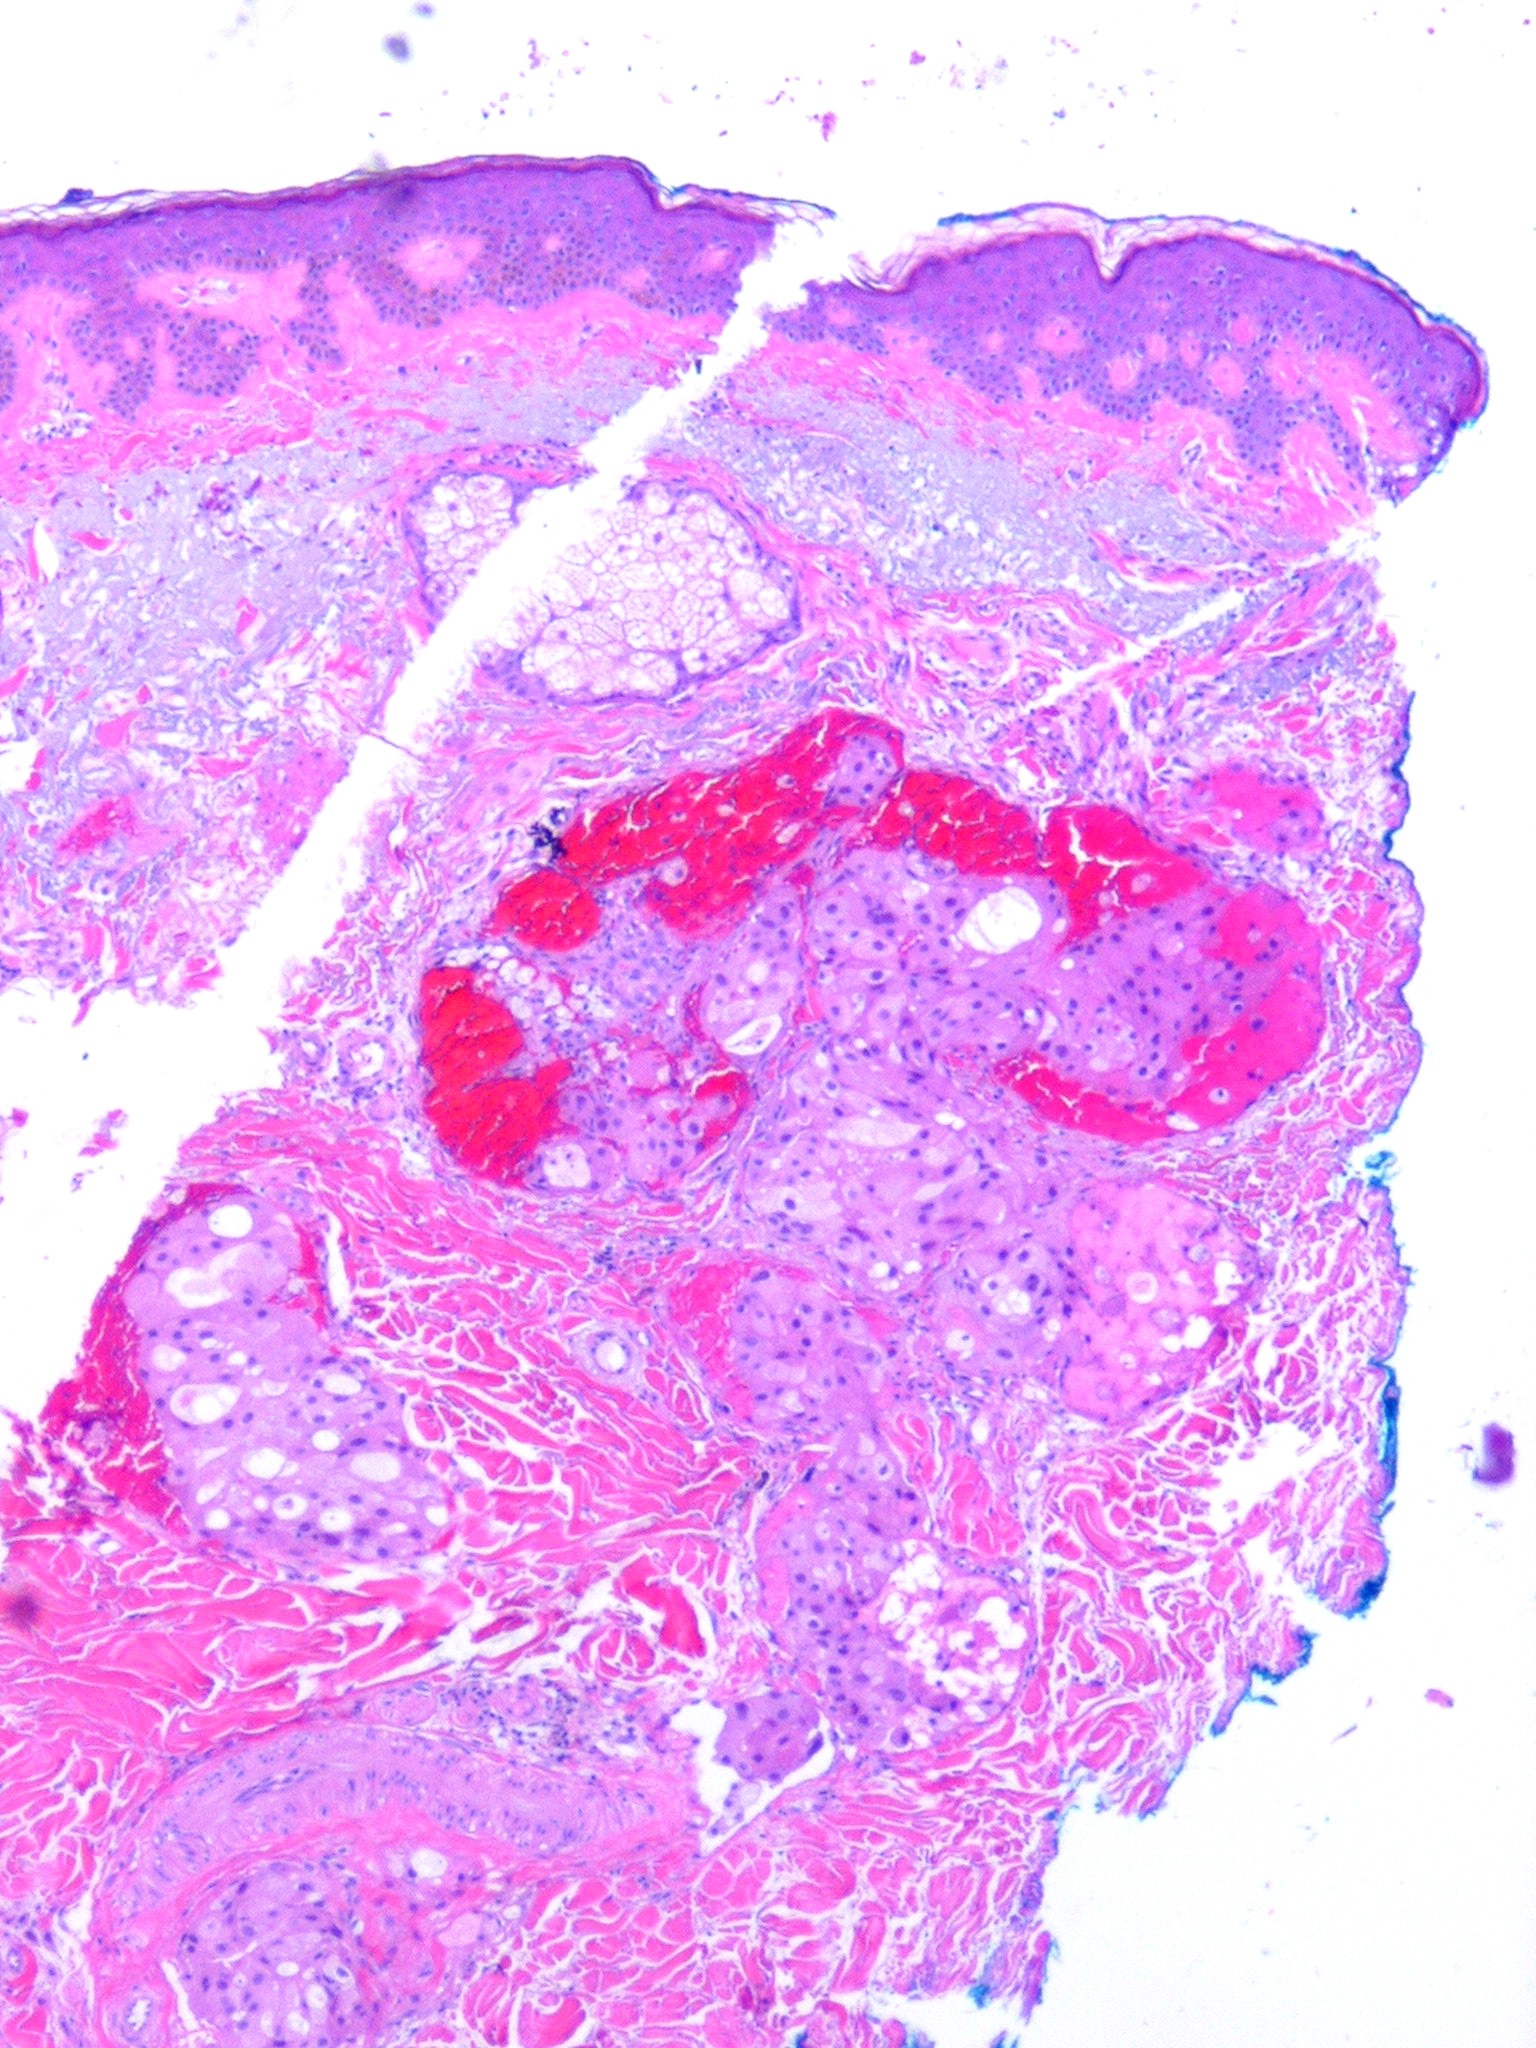

metastasis